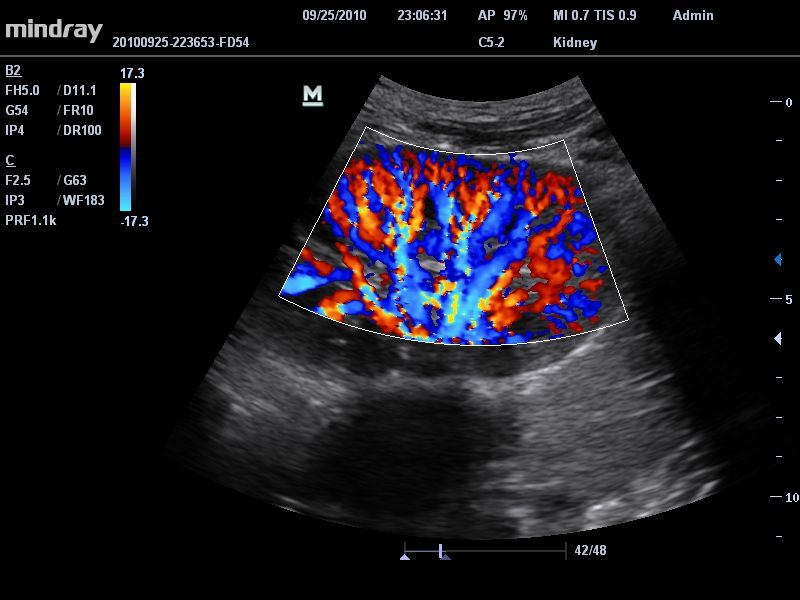

Цветовой допплер:

Да

• Режимы сканирования: B/M/CFM/PDI/Направленный PDI/PW, HPRF, Тканевая гармоника, М- и цветной М-режим.